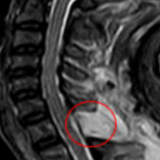

术前核磁检查颈胸段椎管内存在占位性病变,且脊髓已被挤压成线形。

若不尽快手术切除肿瘤,随着肿瘤持续增大,脊髓受压程度会不断加重,进而造成不可逆的神经损伤,最终甚至可能导致四肢瘫痪。接下来,脊柱外科一区主任、主任医师许宇霞带领团队成功为张淮实施了高难度颈胸段椎管内肿瘤切除术。术中快速病检提示肿块为“神经鞘瘤”,这类肿瘤多为良性肿瘤,手术切除后预后良好,复发率低。术后张淮恢复良好,原有颈肩疼痛消失,左上肢麻木无力及右下肢行走无力等症状均显著改善。